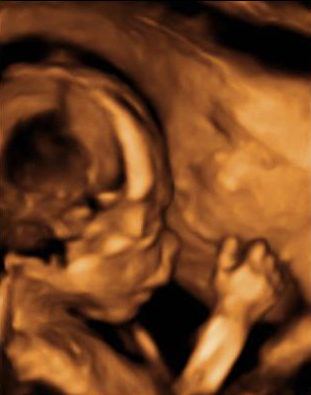

Corazón fetal en el que se aprecia una mancha brillante o foco ecogénito

La imagen de la flecha indica el foco ecogénito en el ventrículo izquierdo.